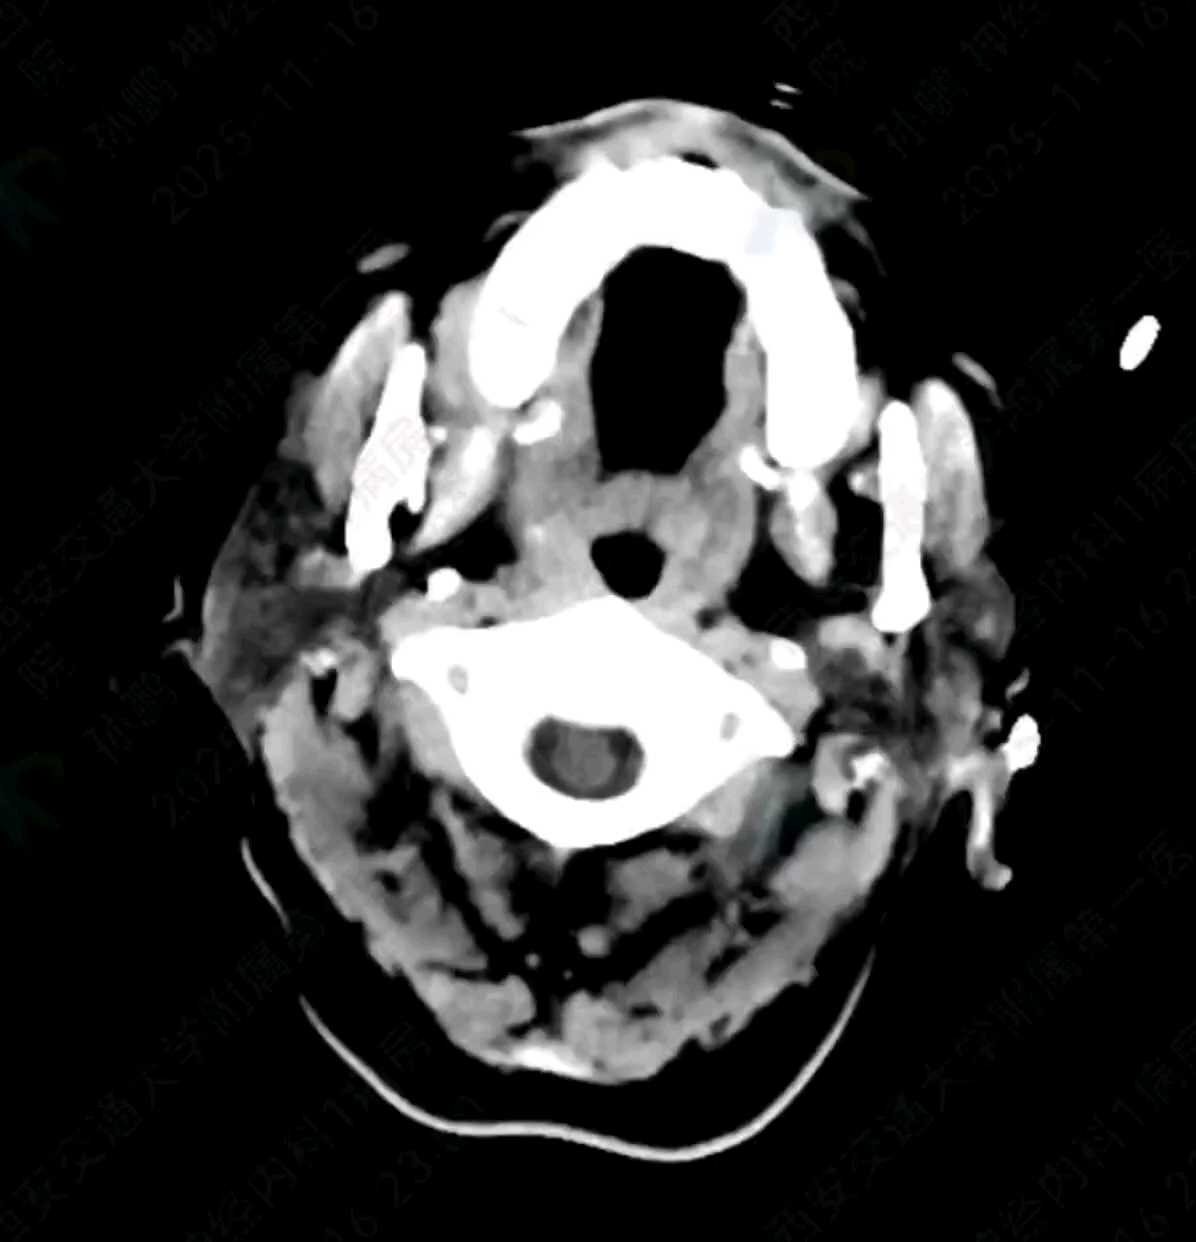

术后6小时复查颅脑CT